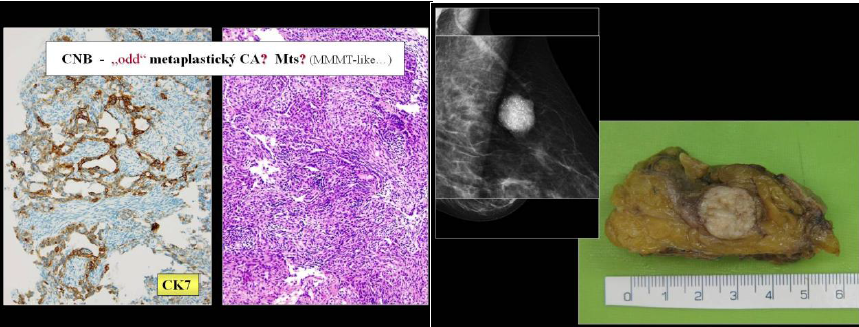

Primární sarkomy prsu představují méně než 1 % všech maligních nádorů prsu a vyjma sekundárního postradiačního angiosarkomu se v písemnictví objevují jen jako sporadické případy dokumentující složitost histologické diagnostiky. Proč právě mléčná žláza, tvořená většinově pojivovou tkání, je výjimečnou lokalitou původu pestré škály maligních měkkotkáňových proliferací, není jasné; důvodem může být např. hormonálně dependentní stroma. Správné rozpoznání mezenchymální histogeneze těchto zde jedinečných lézí navíc komplikuje fakt, že patolog v orgánu, kde karcinom dominuje rutinní diagnostice, s touto ojedinělou morfologickou eventualitou prakticky nepočítá. Pakliže mikroskopicky obraz vůbec odpovídá mezenchymálnímu tumoru, je totiž nejpravděpodobnější, že se jedná o heterologní komponentu metaplastického karcinomu či fyloidního tumoru, kde původní evidentní epitelová složka je významně potlačena. Biologie těchto procesů, kde převládá primitivní vřetenobuněčný/fibrosarkomatózní či ostechondromatózní fenotyp, se však principielně stále více řídí prvotní/výchozí neoplázíí. Morfologická rozmanitost metaplastického karcinomu pak obecně svádí k přeceňování domnělé mezenchymální orientace, zejména při značné plasticitě epitelového imunofenotypu. Např. akantolytický, pseudoangiomatózní karcinom prsu dokáže věrně napodobit diferencovaný primární angiosarkom.

Přednáška ukazuje na krátkých, přehledných kazuistikách náročnost a možné omyly v diagnostice primárních sarkomů prsu - např. synoviální sarkom, maligní schwanom, liposarkom, angiosarkom atd. Patolog musí nejen vnímat i často jen jemné strukturální a cytologické detaily, ale především na neobyčejnou alternativní diagnostickou eventualitu pomyslet a tím efektivně směřovat speciální vyšetřovací metodiky. Je potřeba připustit, že přesný a spolehlivý závěr z limitované punkční biopsie někdy prostě možný není. Vyjádření diagnostických rozpaků ve zprávě není tak vždy jen odrazem odborné nejistoty a je namístě. Možné pochybení pak zkresluje prognostický výhled a terapeutický přístup. Totiž, primární sarkom prsu, jakkoliv je unikátní, není totéž jako metaplastický karcinom resp. maligní fylodes tumor.